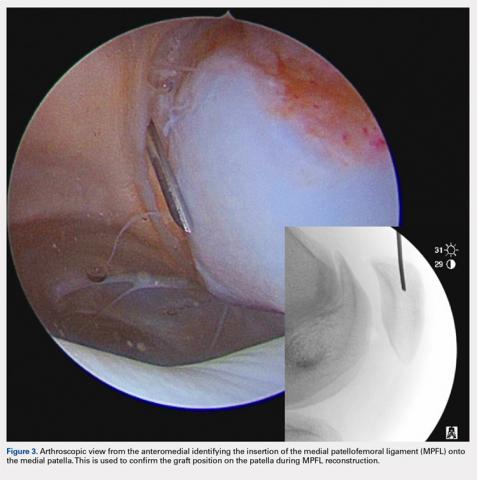

There are 3 methods to identify the insertion of the MPFL into the patella. During the diagnostic arthroscopy, an 18-gauge needle can be used to mark the insertion of the MPFL as visualization of the ligament arthroscopically is often possible (Figure 3). Another useful technique is to follow the inferior aspect of the distal insertion of the vastus medialis oblique (VMO) into the patella. The typical insertion point of the MPFL is immediately distal to the insertion of the inferior aspect of the VMO (Figure 4). It is also helpful to note that the center point of the insertion of the MPFL is at the junction of the proximal one-third and distal two-thirds of the palpable osseous patella. The MPFL origin has been noted to be at the exact midpoint of the chondral surface of the patella or 5 mm proximal (41% of the length of the patella) to the midpoint of the osseous patella.30